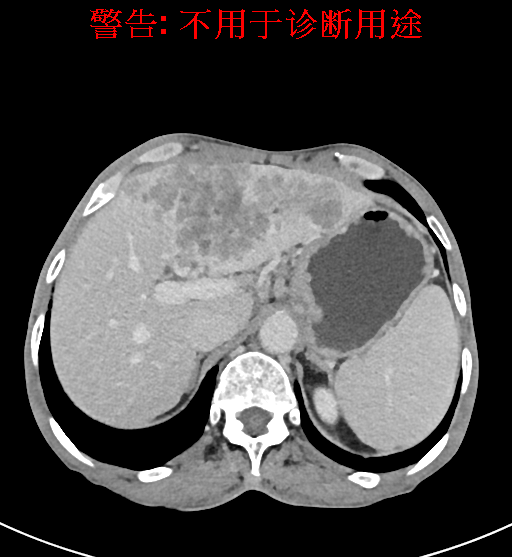

实验室检查: 血常规:WBC 4.89*109/L,RBC 3.64*1012/L, HB 119.00g/L, HCT 35.40%,PLT 123*109/L,RET% 0.48%, RET 0.017*1012/L, IRF 2.00%生化全套:ALT 56.00U/L AST 60.00U/L, LDH 312.00U/L TP 72.08g/L ALB 32.44g/L, GGT 101.00U/L,TBA 21.90umol/L,A/G 0.82,ADA 23.00U/L, PAB 94.20mg/L, CHE 5405.00U/L 肿瘤标志物:CEA 2.80ng/mL CA19-9 11.46U/ml 肝炎全套: HAV-IgM 0.21S/CO, HBcIgM 0.330S/CO, HCV-cAg 0.08S/CO, HEV-IgM 0.03S/CO, HBeAg 6.000S/CO 诊疗过程: CT结果输入海信CAS系统后行3D重建及手术规划后,于2018-5-17局麻下行“经皮肝动脉造影术+肝动脉化疗栓塞术”手术治疗 术前三维重建及手术方案设计: 将0.625mm双源薄层CT资料的静脉期和动脉期Dicom格式文件导入海信CAS系统。 通过调节窗宽窗位调整CT序号,对肿瘤,肝实质,胆囊,下腔静脉,肿瘤,肝动脉、门静脉及肝静脉等进行三维重建;系统自动计算肿瘤体积和肝脏体积。肝脏体积为1563ml,肿瘤体积为537.6ml,通过比对50-60岁正常肝脏体积为1343.28±246.69ml。 手术步骤: 常规准备后,患者仰卧于DSA手术床。常规双侧股动脉区域消毒,铺巾。2%利多卡因局部麻醉右侧股动脉区成功后,应用Seldinger技术穿刺右侧股动脉,置入5F动脉鞘。送5F 肝导管至腹腔干、肝动脉造影,肝区可见团块状及多发结节状肿瘤染色、侵犯门静脉左支。静脉推注维瑞特5mg后,透视下将微导管分别超选择至各支肿瘤供血动脉内,应用雷替曲塞4mg+奥沙利铂50mg+表柔比星20mg +LP 10ml的混合液及适量350-560um明胶海绵进行栓塞,后造影示栓塞适量,退出导管、血管鞘,局部压迫10min,加压包扎。患者术中未诉不适,术后平车安返病房。随访情况: 患者术后3月复查上腹CT示肝左叶病变活性残留,腹腔内、腹膜后多发略大淋巴结,部分较前略减小,今患者为求进一步诊治,与我院再次行“肝动脉造影+经导管肝动脉栓塞术”,术后2周无明显不适 术前CT检查:动脉期

静脉期

平衡期